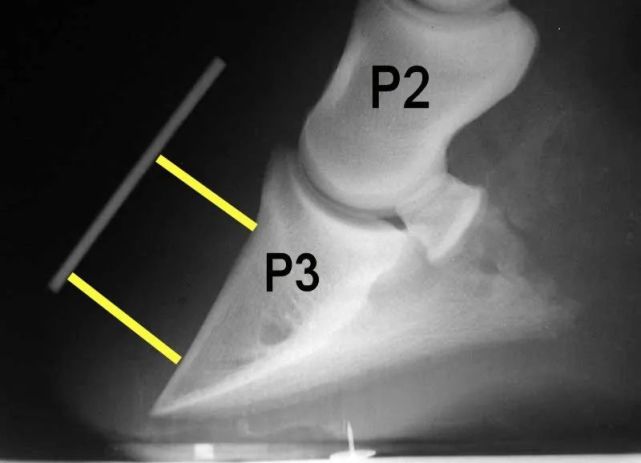

这听起来已经很疼了,但拆开马蹄还有更多惊吓。马蹄后的骨头叫做蹄骨,有点像一块削尖的三角形刀片。

图片

从侧面看,马的蹄骨就像刀刃一样锋利。图片来源:wikipedia